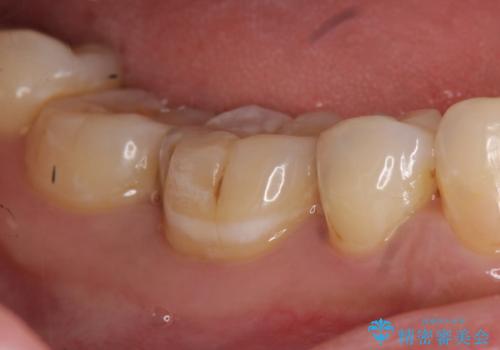

右下5は虫歯が大きかったため、虫歯を除去後、オールセラミッククラウンによる補綴を行いました。

今回用いたオールセラミッククラウンはジルコニアフレームという白い素材の上にセラミックを盛っているため、審美性が非常に高いのが特徴です。

また、ジルコニアは人工ダイヤモンドの材料にも使われているほど高い強度を持っており、そのためオールセラミッククラウンは審美性だけでなく、奥歯やブリッジの補綴も可能とするクラウンです